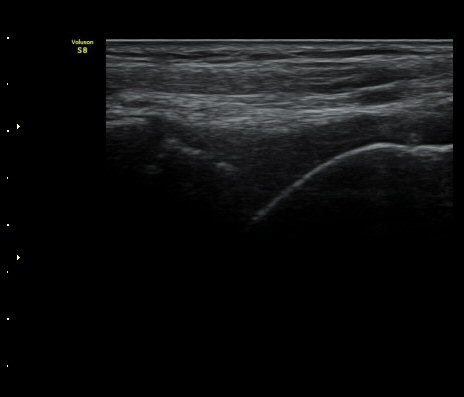

¹ß¸ñ°üÀý Á¾´Ü¸é°Ë»ç¿¡¼­ °üÀý³» ¼ö¾×Àú·ù°¡ °üÂûµÈ´Ù(±×¸² 1).

ÃÊÀ½ÆÄÅõ½ÃÇÏ ºÎÇϰ˻翡¼­ ºñ°ñ°ú °ß¿­°ñÀý °ñÆí»çÀÌ¿Í ºñ°ñ°ú °Å°ñ »çÀ̰¡ ¹ú¾îÁø´Ù

(樨毢 1)